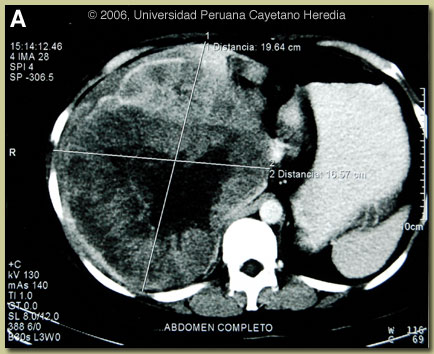

| Diagnosis: Chronic infection with hepatitis B complicated by hepatocellular carcinoma. |

The official MRI report described a solid 20 cm diameter lesion with ill-defined borders and of heterogeneous density occupying the entire right lobe of the liver. The mass was noted to be indenting the hepatic flexure of the colon but there was no indication of any invasion of the kidney or other organs and there was no evidence of any peri-hepatic or intra-abdominal fluid. The right hemi-azygous vein was noted to be dilated but MR flow studies indicated no thrombus in this vein or in the portal vein or vena cava. The only differential diagnosis based on the imaging study was between hepatocellular carcinoma and hepatocarcinoma of the fibro-lamellar type. More than 400 million people worldwide are chronic carriers of hepatitis B virus (HBV). Over 80% of the half-million annual cases of liver cancer are caused by viral hepatitis with two-thirds of these due to HBV. Up to one-third of the world’s population has been infected at some time with HBV and 5% are chronically infected. Three-quarters of those with chronic HBV in the world are from China and sub-Saharan Africa with southeast Asia also having very high rates. Prevalence of chronic HBV carriage in those regions is 10-20% with most infections occurring in the neonatal period or during early childhood, thus emphasizing the importance of peri-natal vaccination strategies. In contrast, in countries of North America, Europe and Australia where infections occur primarily during adolescence or adulthood, prevalence rates are <0.5%. While none of the South American countries as a whole qualify as highly endemic for HBV, rates as high as those found in China can be found amongst native Amerindian populations from the Amazon basin and related ecosystems [Cad Saúde Pública. 2003 Nov-Dec;19(6):1583-91]. Of note, there is also an association with a high level of infection with hepatitis D virus among the chronic HBV carriers in the Amazon. In samples taken from various sites in the Maranon and Madre de Dios regions of Peru, prevalence of HBV infection at some time during life (rate of Anti-HBc) is from 69-74% with an HBsAg carriage rate of 3.9-12.1%, and Anti-HDV rates of 2.5-9.0% amongst HBsAg carriers. In the transition Andean valleys and the high jungle surrounding the Peruvian Amazon (Huanta, Abancay) rates are 82% for Anti-HBc, 16% for HBsAg, and 18% of HBsAg carriers are positive for Anti-HDV. Our patient was not born in a typical endemic area but a complete epidemiologic history on parents and grandparents was not available. The risk of chronicity with HBV varies greatly according to age of acquisition of the infection. For neonates and children younger than 1 year, the risk of the infection becoming chronic is 90%. Between ages 1-5 years, the risk is 30% and for those older than 5 years at time of infection the risk decreases to about 2%. Large powerful epidemiologic studies support the relationship between chronic HBV infection and hepatocellular carcinoma. A minimum of 20-30 years seems to be required for the development of cancer so that cases appear in the 20-30 age group in hyperendemic areas with predominant peri-natal infection, and in the 6th decade of life in lower endemic areas. The male:female ratio is 3:1 and risk is higher in those who are HBeAg positive. While most hepatocellular cancer due to HBV develops on a background of pre-existing cirrhosis, from 15-45% does not. Hepatocellular carcinoma is an aggressive malignancy, usually detected late, with median survival from 6-20 months. Partial hepatectomy in situations where cure is possible (no radiologic evidence of vascular invasion or metastases) is the optimal treatment for hepatocellular carcinoma. Long-term relapse-free survival rates average 40 percent or better in carefully selected patients with small (<5 cm="" tumors="" and="" good="" underlying="" liver="" function="" nbsp="" however="" there="" is="" no="" general="" rule="" regarding="" tumor="" size="" for="" selection="" of="" patients="" resection="" advanced="" or="" non-resectable="" disease="" a="" number="" options="" including="" combination="" chemotherapy="" radiofrequency="" ablation="" embolization="" exist="" but="" none="" optimal="" infectious="" agents="" are="" associated="" with="" at="" least="" 16="" different="" cancers="" among="" which="" hepatocarcinoma="" hbv="" cervical="" cancer="" hpv="" gastric="" em="">H. pylori) are the most important. Follow-up MRI 7 months post-operatively [Image E] showed compensatory hypertrophy of the left lobe with formation of a large nodule in the surgical bed consistent with recurrent disease. No retroperitoneal or mesenteric adenopathy. AFP levels were rising once again. We wish to thank Drs. Raul Gutierrez (Infectious Diseases), Luis Tacsa (Pathology), and Eloy Ruiz (Surgery) of the INEN (Instituto Nacional de Enfermedades Neoplasticas) in Lima for discussion, advice, and the images for this case.